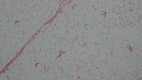

Figure 6. Histopathological image showing a lipoma (2 vessels present)

Hematoxylin and Eosin (H&E) stain, Magnification x2